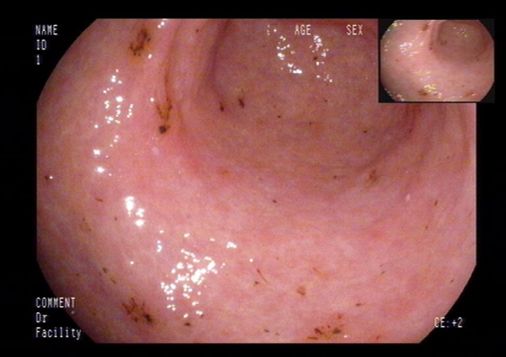

初步诊疗过程:入院后检查:血常规:单核细胞百分比 10.10%,淋巴细胞百分比 19.40%;尿常规:尿蛋白 +-;粪常规未见异常;肝功能:总胆红素 22.10umol/L,直接胆红素 12.83umol/L,谷丙转氨酶 88IU/L,谷草转氨酶 107IU/L,总蛋白 43.8g/L,白蛋白 24.3g/L,球蛋白 19.5g/L,总胆汁酸 31.4umol/L;血脂:总胆固醇 1.64mmol/L;电解质:钙 1.81mmol/L,磷 0.77mmol/L;凝血:凝血酶原时间测定 15.5秒,凝血酶原时间比值 1.46,活化部分凝血活酶时间测定 37.5秒,D-二聚体 3110.00ug/L,纤维蛋白(原)降解产物 9.56mg/L;肿瘤标志物:糖类抗原125 303.60U/ml,余项基本正常;肝炎系列+HIV+TP、T-SPOT阴性;腹水肿瘤标志物:糖类抗原125 390.10U/ml;腹水结核分枝杆菌IgG抗体阴性;复查腹水常规、生化仍提示漏出液;腹水培养阴性;PPD试验阴性;自身抗体系列未见异常。腹部超声:脂肪肝、胆囊壁毛糙、腹水;腹部血管彩超:肝段下腔静脉、门静脉及肝静脉内未见明显栓子回声。肝纤维化无创检测示:硬度值 36.5kPa。胃镜检查:食管静脉曲张、门脉高压性胃病、十二指肠多发溃疡。初步诊断为肝硬化失代偿期。给予利尿、抗感染、保肝、补白蛋白、放腹水、抑酸等治疗。患者病情无改善。

上消化道内镜: